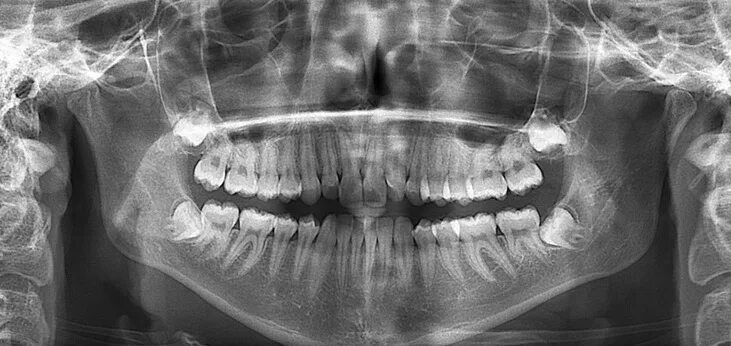

Снимок ротовой полости